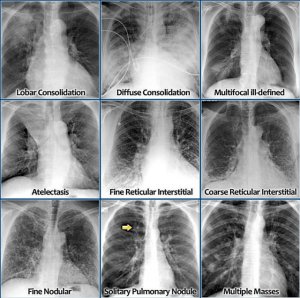

Det radiologiske team gennemgår systematisk røntgen af thorax fra teknik og anatomi, traume til lungesygdom og meget mere. Kursets formål er, at de kliniske læger får grundig undervisning i RU thorax som værktøj i dagarbejde og i vagterne.

Billede fra: https://radiologyassistant.n